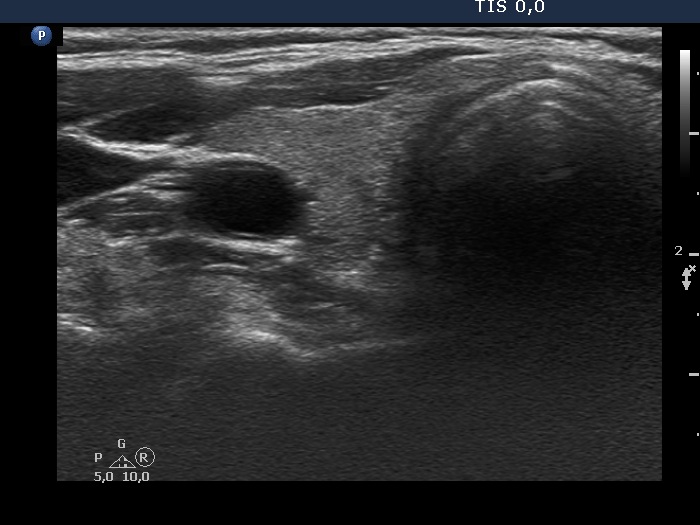

Ultrasonography. The thyroid was echonormal. There were several nodules in the left lobe. The largest in the upper pole presented all but one of the possible suspicious characteristics, it was deeply hypoechoic, had irregular margins, a microcalcification and showed abutting and bulging contours. Moreover, the intranodular vascularization was irregularly increased. One of the other lesions presented back wall figures while the third one showed taller-than-wide shape.